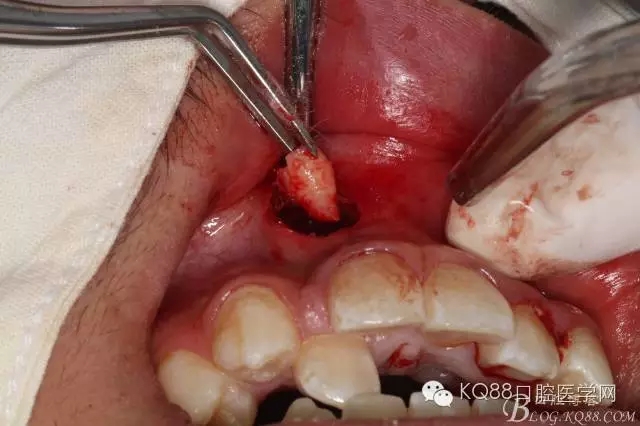

圖5.經(jīng)過仔細(xì)認(rèn)真的術(shù)前CBCT影像檢查分析,考慮手術(shù)進(jìn)路及操作性,局部浸潤麻醉下,遂從唇側(cè)前庭溝處做弧形小切口、翻瓣。渦輪鉆去骨后的臨床情形:完美的弧形切口。去除唇側(cè)的骨板、顯露出部分多生牙的牙根和少量牙冠,位置之高,令人吃驚、一定要注意11的牙根,防止損傷11根尖。